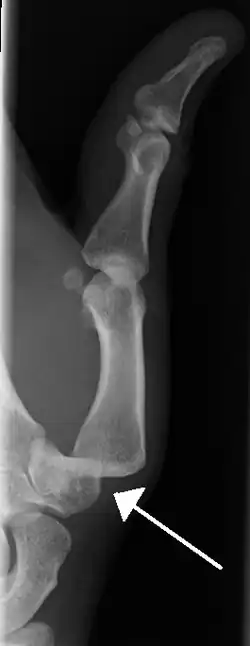

| A traumatic dislocation of the tibiotarsal joint of the ankle with distal fibular fracture. Open arrow marks the tibia and the closed arrow marks the talus. | |